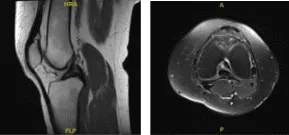

MRI results were presented and shown single slice visualization of a small medial meniscus tear. Trace joint effusion. The ACL is unremarkable, without evidence of tear, degeneration, or postoperative change.

MRI -3 T Left Knee Non-contrast